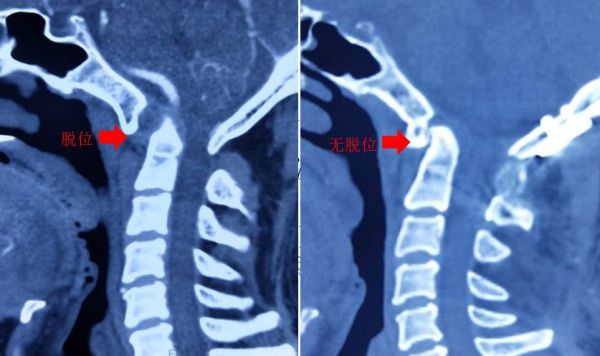

2.儿童轻微外伤后或无显著原因,晨起后、感冒后出现的歪脖子、颈部疼痛、转头困难,很可能是因为“寰(huan)枢(shu)关节半脱”。

寰枢关节,就是人颈椎的第一节和第二节,由于儿童寰枢椎韧带松弛,轻微外伤或者姿势不良特别容易“关节脱位”。在脱位的时候,游离的枢椎齿状突(第二节颈椎),会压迫到脊髓,从而引起颈部疼痛、头晕、转头困难的症状。

如果孩子头不能歪的症状持续了好几天,往往就不是“落枕”这么简单了,需要尽快去医院进行CT检查。一旦确诊,就要佩戴颈托,甚至需要手术治疗。